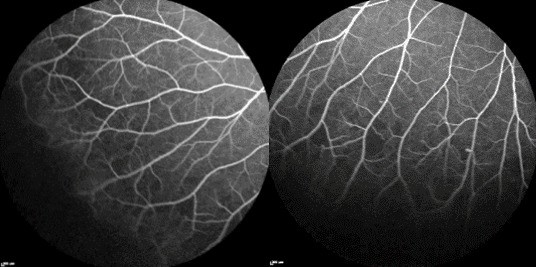

The patient returned two months later for his follow-up with ophthalmology to evaluate his sickle cell retinopathy. He reported no changes to vision. He denied any new flashes or floaters. His visual acuity without correction was 20/40, PH to 20/20-1 OD, 20/25 OS. His eye pressure was within normal limits, and his slit lamp exam was unremarkable for any new anterior segment findings. Dilated fundus examination was normal in the right eye (Fig. 3A). His left eye showed a stable neovascular frond in the temporal arcade (Fig. 3B). On the same day, fluorescein angiography was performed, which confirmed the presence of a proliferative complex with a surrounding area of capillary non-perfusion in the left eye. The right eye was also found to have patchy areas of capillary non-perfusion in the temporal retina (Fig. 4A-B). At this time, treatment was recommended for the left eye with panretinal photocoagulation.

Figure 4 (A,B).Late phase fluorescein angiograms illustrate areas of patchy capillary non-perfusion in the temporal peripheral retina.